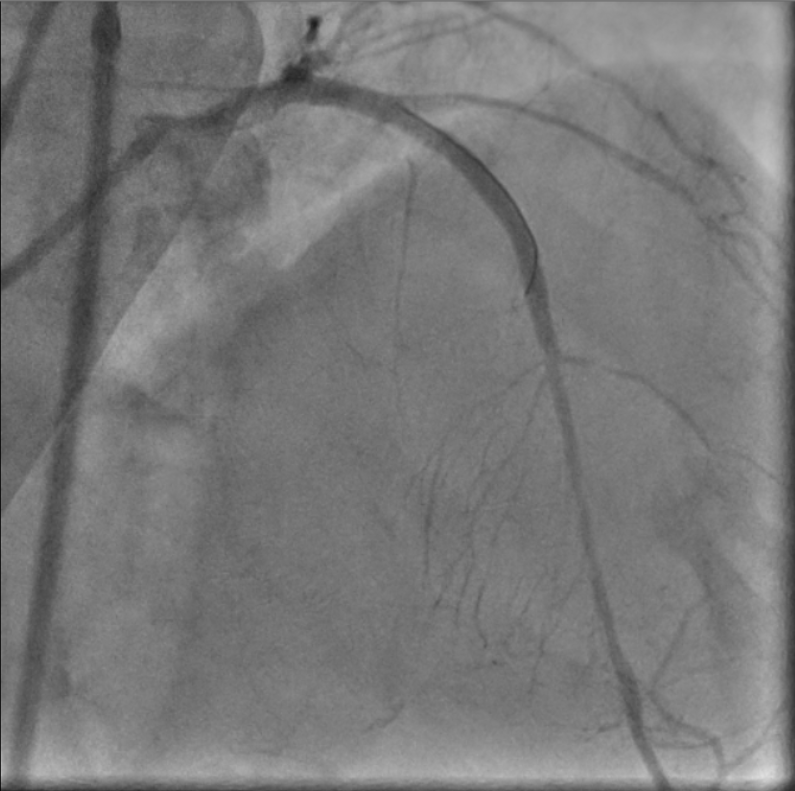

As patient is having cardiogenic shock from a LM occlusion and refusal of CABG, a high-risk, mechanically-supported PCI was undertaken. An IABP was inserted via the left femoral artery for hemodynamic support.Right femoral artery approach. 7Fr EBU 3.5 Guide. LAD and LCx were wired with microcatheter support. 2.0 balloon was used to predilate the LM-LAD lesion, TIMI 3 flow restored.IVUS was performed, showing heavily calcified plaque throughout the LM and LAD. Based on IVUS sizing (LM: 4.5mm, pLAD: 4.0mm), predilation with NC balloons followed by Intravascular Lithotripsy (IVL) with a 3.0 Shockwave balloon for 70 cycles were performed.A 2.75/40mm DES was placed in the mid-LAD and a 3.5/24mm DES was deployed from the ostial LM into the proximal LAD. POT in the LM using a 4.5 NC balloon, followed by post-dilation of the proximal LAD with a 4.0 NC balloon.Post-angiography revealed a jailed D1 with TIMI 0 flow. Rewiring to D1 was reattempted successfully with a CTO wire. Switched back to workhorse wire, dotted and predilated with 1.5 semi-compliant balloon. However IVUS showed wire likely true-false-true with ostial D1 in subintimal. Decided not to further intervene on D1.Final IVUS showed satisfactory results. Angiogram after adenosine showed regained flow in D1, TIMI 3 flow in both LAD and D1. Patient remained hemodynamically stable on IABP support post-procedure.

Case Summary